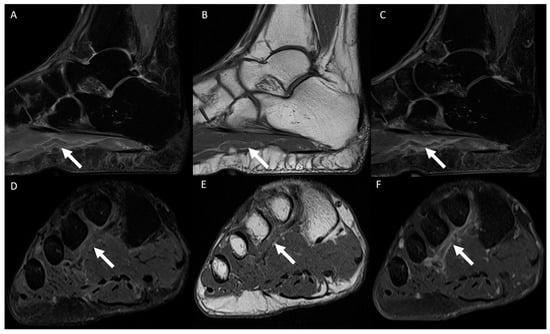

3.2. Distribution of MRI Findings